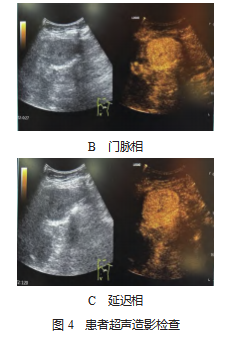

患者,女性,62 岁,因上腹不适于 2023 年 4 月初行 肾 CT 检查,提示左上腹肿物,见图 1 。4 月 20 日行超声 检查提示:左上腹部(脾脏内侧,胃底外侧)一大小约 6.5 cm×4.8 cm×6.1 cm 低回声实性团块, 边界清晰, 形态规 整,内部回声欠均匀, 可见不规则无回声区, 彩色多普勒血 流显像(CDFI):内部及周边血流信号较丰富, 可见一粗 大血管供应肿物, 其来源未明确, 见图 2.饮水后观察该团 块位于胃底前方, 与胃、脾、肾无关, 考虑来源于系膜, 见 图 3.2023 年 5 月 6 日行超声造影检查:肘静脉团注注射用 六氟化硫微泡(Bracco Suisse SA,注册证号 HJ20171213. 规格: 59 mg 六氟化硫),动脉期:可见粗大血管从肿物边缘向内开始灌注,呈周边向中央不均匀性增强;门脉期: 呈高增强,中央部分低增强;延迟期:中央区低增强基本 廓清,周围呈等增强,其相邻脾脏灌注及撤退模式均与该 团块不同,见图 4-A、4-B、4-C,考虑间质瘤(来源于肠 系膜),不除外其他新生性肿瘤可能。2023 年 5 月 10 日 行腹部核磁平扫及增强检查:左上腹膈下脾脏前上方椭圆 形稍长 T1、稍长 T2 信号肿物。核磁增强:病灶强化,其 旁可见脾动脉分支延伸入病灶内,考虑左上腹脾外血管瘤 (脾动脉供血)或肠系膜间质瘤,见图 5-A、5-B。

3.3影像学诊断 SFT 最常见的超声表现为边界清楚、 边缘光滑的圆形或椭圆形实质性肿块,低回声或中等回 声,回声均匀或欠均匀,血流丰富,多呈分枝状彩色血 流,血管阻力较小 [6] 。本例肿物呈边界清楚,形态规则的 低回声,位于胃底和脾脏之间,与胃底关系密切,为排除来源于胃底的外生性间质瘤,饮水后发现其与胃壁无关,进一步超声造影表现为粗大血管供应的“快进慢退”不均匀增强,考虑可能与肿块血供来源于脾动脉分支有关,其内低增强考虑部分坏死。核磁成像中良性病灶均为单发,肿瘤边界清楚,轮廓光整,占位效应不明显,较大病灶对 周围组织呈推移改变。良性病灶 MRI 检查密度及信号均 匀,体部病灶低于肌肉组织,肿瘤内部可见条状高信号, T1 加权成像(T1WI)呈低信号,扩散加权成像(DWI ) 序列呈低信号 [7] 。恶性病灶边缘呈分叶状,部分为多发病 灶,侵及相邻肌肉、骨骼等组织。较大病灶、恶性病灶密 度及信号不均匀,可见囊变坏死区。增强扫描病灶强化方 式多样,有报道表明,由于肿瘤内的病理组成成分不同所 致,但大部分均为中度或明显强化,强化主要与致密胶 原纤维和细胞致密区、囊变或黏液样变情况有关 [8] 。动态 增强扫描对于肿物的定性具有明显的帮助,动脉期多呈轻 度- 重度强化,静脉期持续强化,呈典型的“地图样”强 化,本病例中可见与之相符的强化方式。